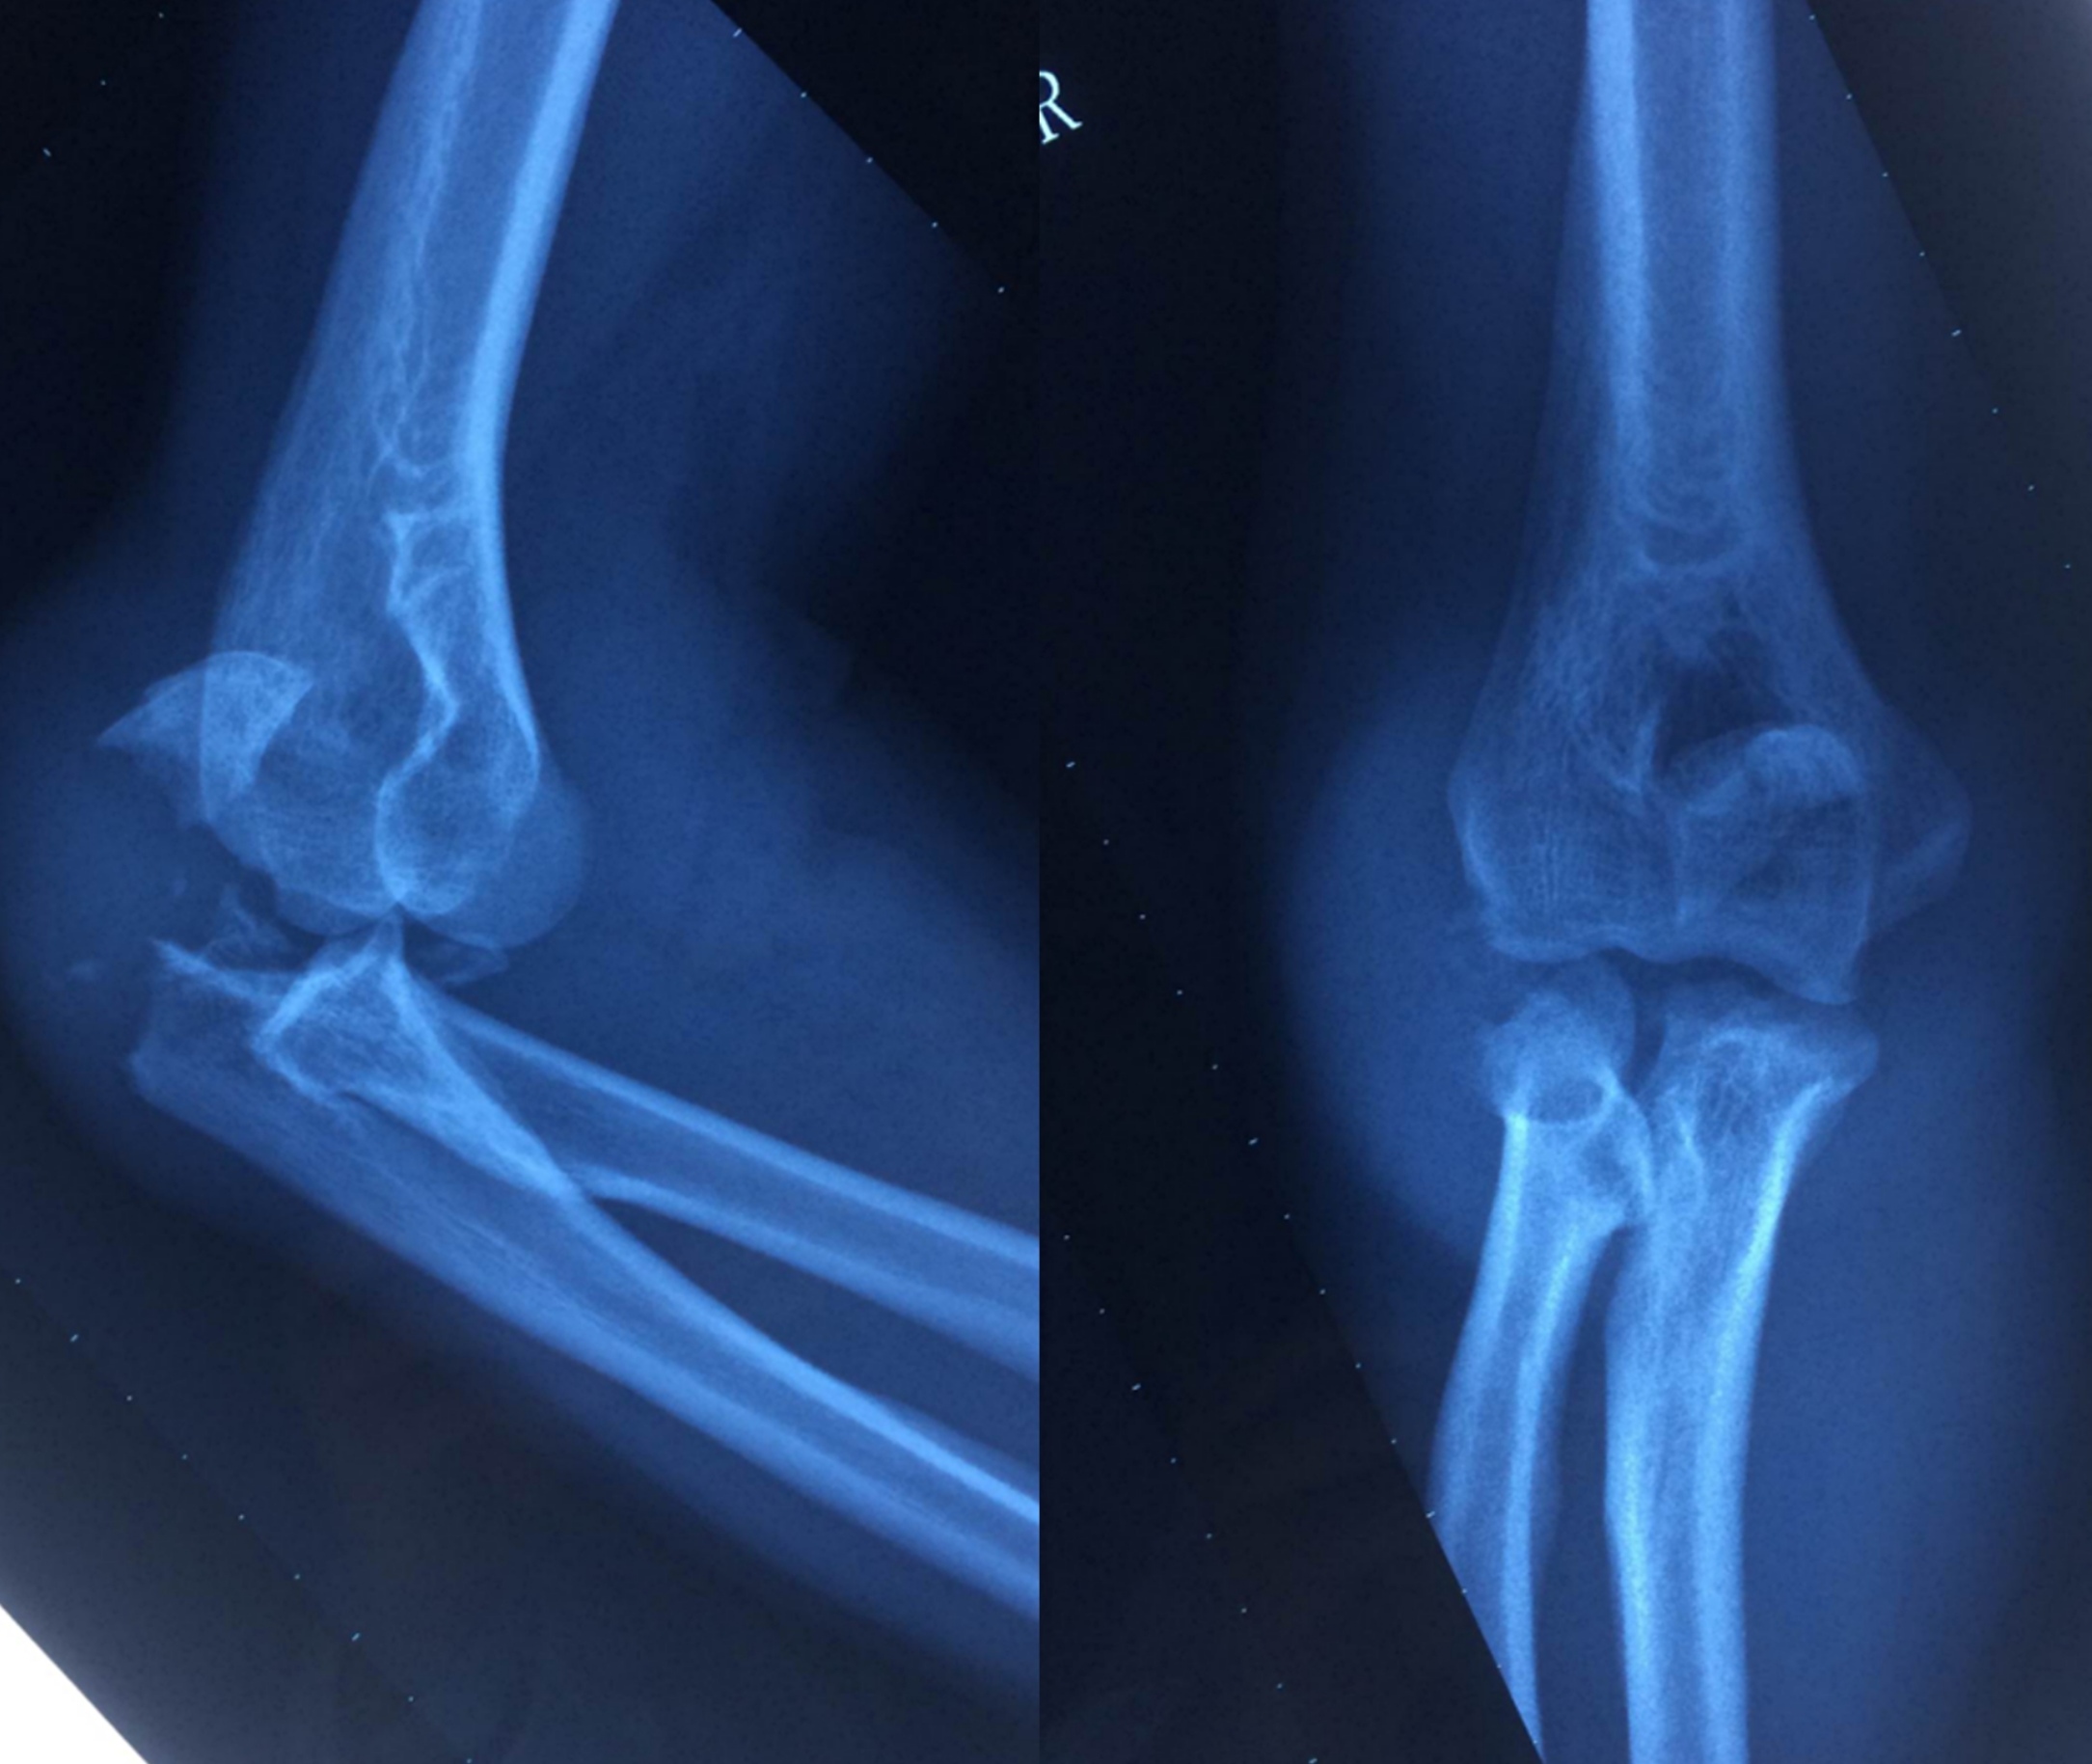

病例讨论会各位骨科专家将围绕一则“创伤性肘关节不稳定”病例进行探讨。

病例影像资料